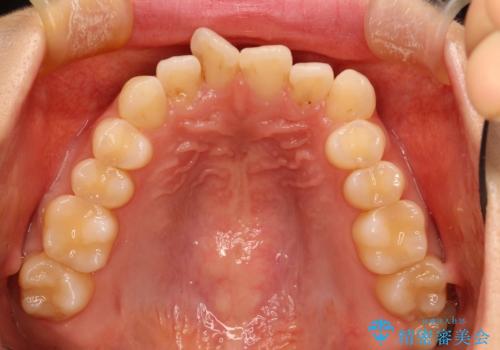

前歯のガタガタをインビザラインで目立たず矯正

- 目立たずに前歯を矯正したいとのことで来院されました。

歯と歯の間にわずかに隙間を作りスペースを確保し、インビザラインにて矯正を行うこととなりました。

前歯の微調整に少し時間がかかりましたが、整った歯並びにすることができました。